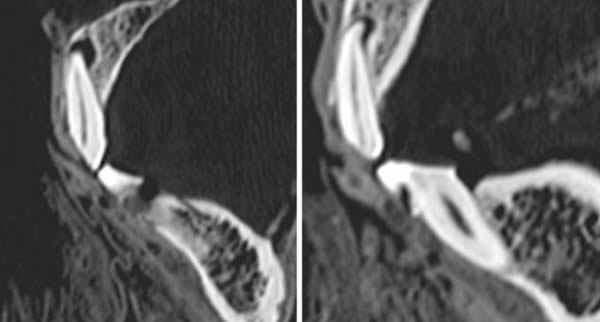

CT片显示了木乃伊左边第一颗门牙(左图)和右边第二颗门牙(右图)的磨损状况。